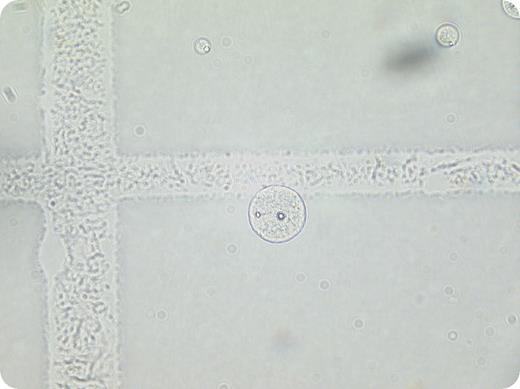

A diagnosis of lymphomatous meningitis was made and liposomal cytarabine (DepoCyte) was administered intrathecally. Two weeks later, clinical improvement was noted and further DepoCyte was administered. On that occasion, the CSF white cell count was 0.08 × 109/L. This was an unexpected finding given the clinical improvement. Repeated examination of the CSF revealed that the “white cells” were DepoCyte particles rather than malignant lymphocytes. These particles were not visible on cytospin preparations, either when CSF was spun alone or when it was resuspended in albumin, suggesting that the particles were too fragile to remain intact during cytospin preparation.

Intrathecal DepoCyte is composed of cytarabine held within aqueous chambers and encapsulated by lipid bi-layers. Use of this sustained-release formulation reduces the number of intrathecal injections required. It is important to recognize these particles as spurious elevation of CSF white cell counts, rather than evidence of progressive disease.